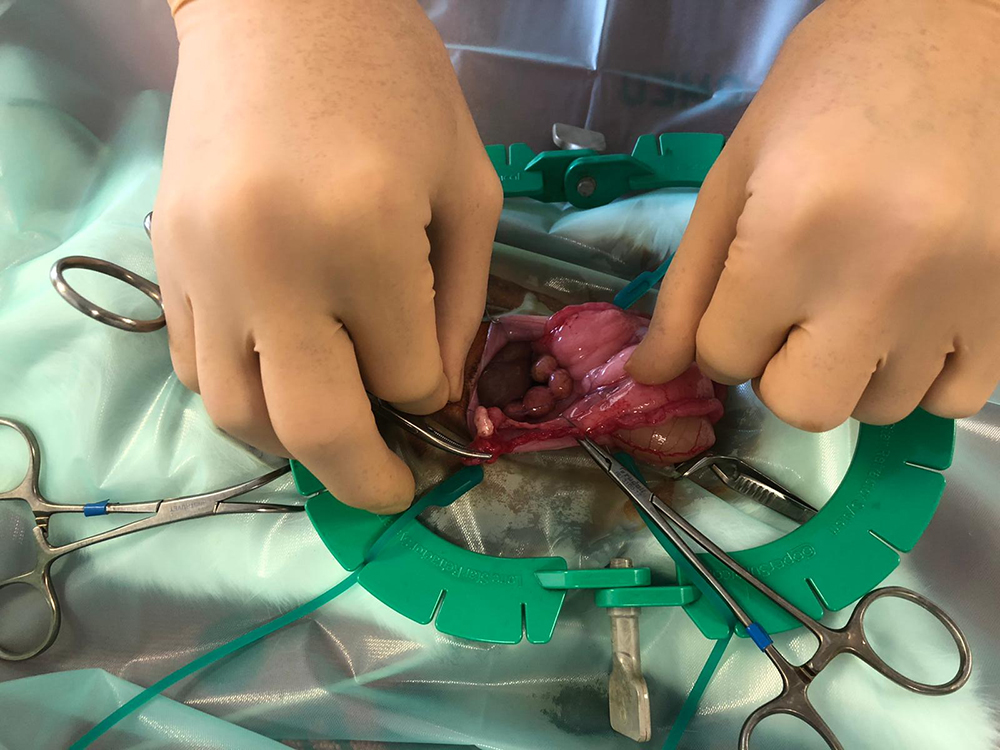

Nu kan de buik geopend worden, tot vlak voor het bekken. Om de buik open te houden, wordt de “lone star retractor” geplaatst. Hiermee is er goed zicht en werkruimte te verkrijgen. De eierstokken liggen bij het konijn vrij ver naar de zijkant, de darmen liggen vaak in de weg en zijn erg fragiel. Met de “lone star retractor” kan de sterilisatie veiliger worden uitgevoerd.

Na het afbinden van de bloedvaten worden de eierstokken en de baarmoeder verwijderd. Hierbij wordt goed opgelet dat ook daadwerkelijk de hele eierstok verwijderd wordt, wat soms lastig te zien is door het vet eromheen.